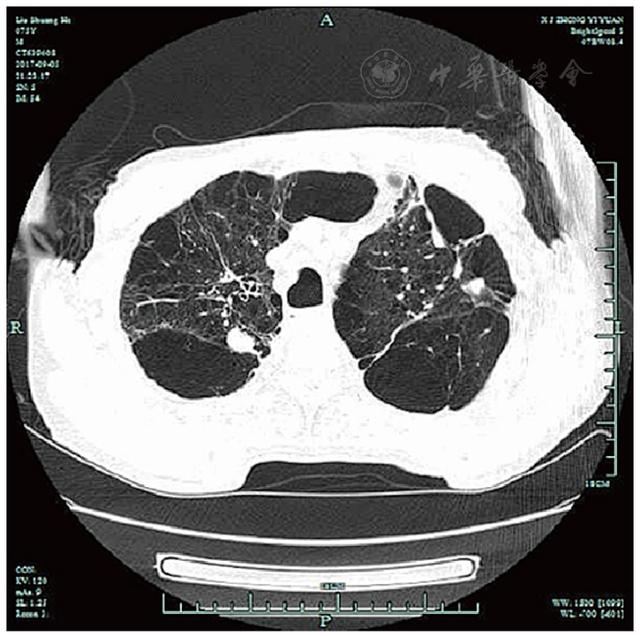

共317例TOPD患者完成影像學檢查。TOPD患者肺部CT顯示多處鈣化結(jié)節(jié)等結(jié)核瘢痕,部分患者存在一定程度的肺氣腫和支氣管擴張征象,見圖1,圖2,圖3。TOPD患者左肺上、舌、下葉的結(jié)核瘢痕陽性分別為176例(55.5%)、120例(37.9%)和126例(39.7%),右肺上、中、下葉的結(jié)核瘢痕陽性分別為215例(67.8%)、142例(44.8%)、168例(52.9%);左肺的支氣管擴張征象主要集中在左肺舌葉,右肺主要位于中葉、下葉;肺氣腫在雙肺間分布較為均衡,見圖4。

Figure 1

Figure 1 Pulmonary imaging findings of TOPD patients